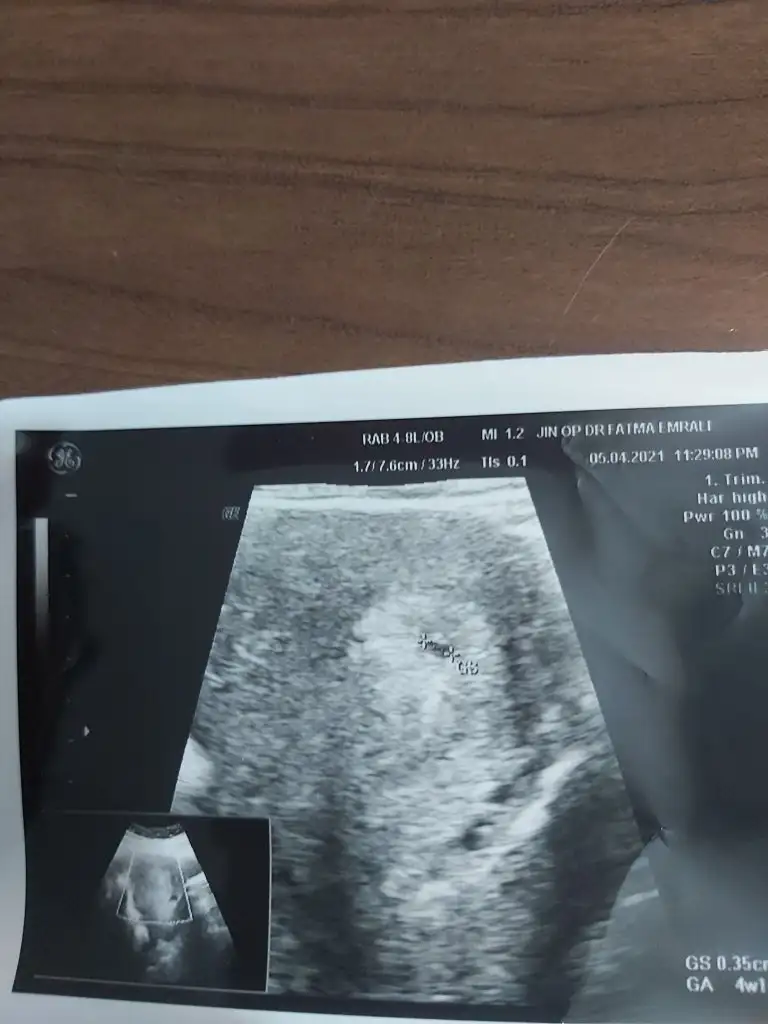

Merhaba 7 hafta 5 günlük burada karından ultrasom abdominal cinsiyet tahmini alabilir miyim bende şimdiden teşekkür ederim.

Ramzi teorisine göre ( bilimsel bir araştırma sonucuymuş ve %85 doğruluğu varmış). İlk 6-8 haftalık ultrason görüntüsüne göre bebeğin kesenin içersinde soldan ya da sağdan girişine göre cinsiyet tahmini yapılıyor. Bilimsel olunca tecrübeli annelerimiz yada anne adaylarımızdan yardım istiyoruz. Doğruluğu var mı öğrenmek adına :) Bizleri aydınlatırsanız çok seviniriz. bu teorieye göre;

Karından bakıldıysa eğer,

Soldan girmiş gözüküyosa gerçektede solmuş ve ERKEK,

Sağdan girmiş gözüküyosa gerçekte de sağmış ve KIZ,